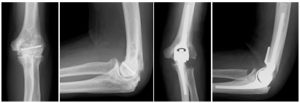

人工肘関節

人工肘関節1

リウマチ肘による痛みと可動域制限に対して、人工肘関節置換術を施行、痛みなく可動域も良好です。

人工肘関節2

肘関節骨折に対し他院で手術を受けられましたが、肘の痛みと運動制限が残存し人工肘関節置換術を施行しました。痛みは消失し、可動域もほぼ正常に回復されました。